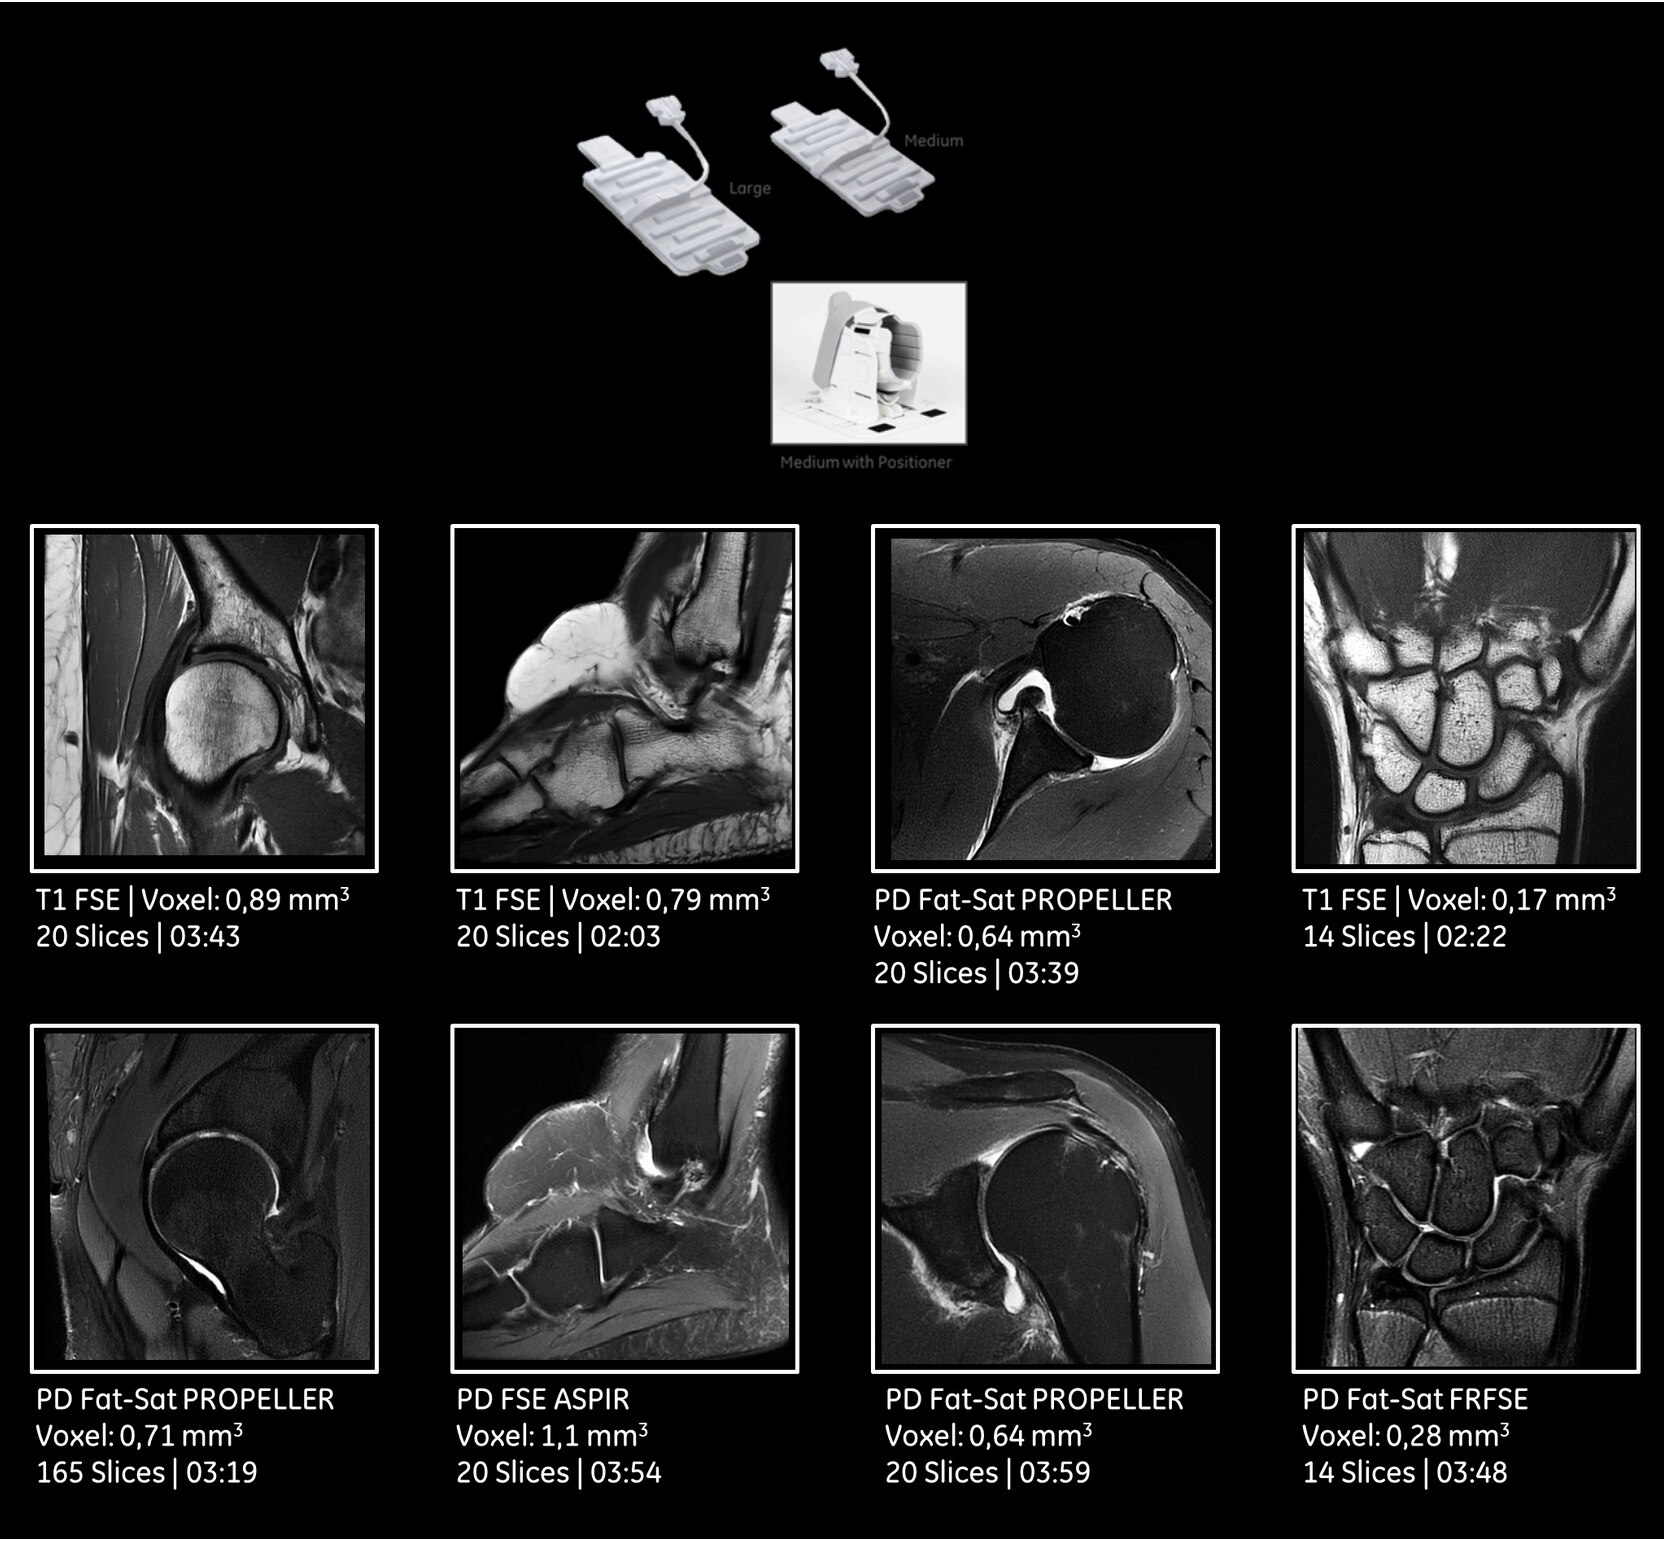

«SIGNA Pioneer с набором гибких 16-канальных катушек значительно повысила нашу уверенность при сложных обследованиях опорно-двигательной системы. Теперь мы можем соответствовать потребностям пациентов с различными анатомическими особенностями и требованиями».